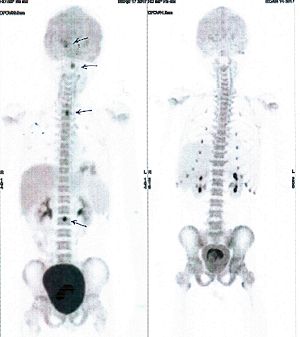

Below are some of the cases, from more than 80 cases we have treated so far with good results. When reading the PET/CT scans, the picture on the left is before treatment, and the picture on the right is after treatment. The intensity of black represents the activity of the cancer, but some black areas are not cancer: brain, heart, radioactive urine in bladder. For the heart, the intensity of black depends on the number of hours of fasting: if more than 10 hours, the heart is not even black, but if fasting is less than 6 hours, it is very black. The intensity of black in the brain can be variable in different scans depending on the brain activity at the time of the scan. The intensity of black in the radioactive urine can also be variable due to the hydration of patients and the time of injection of diuretic.

CASE NO: 3 (PROSTATE CANCER)

A middle-aged man with castration resistant prostate cancer, having failed all currently available cancer treatment, was very weak, and getting worse every day. The PET/CT scan showed he had massive bone metastases. After a few treatment, all the bone metastases went into remission. About 6 months later, he is still in remission.